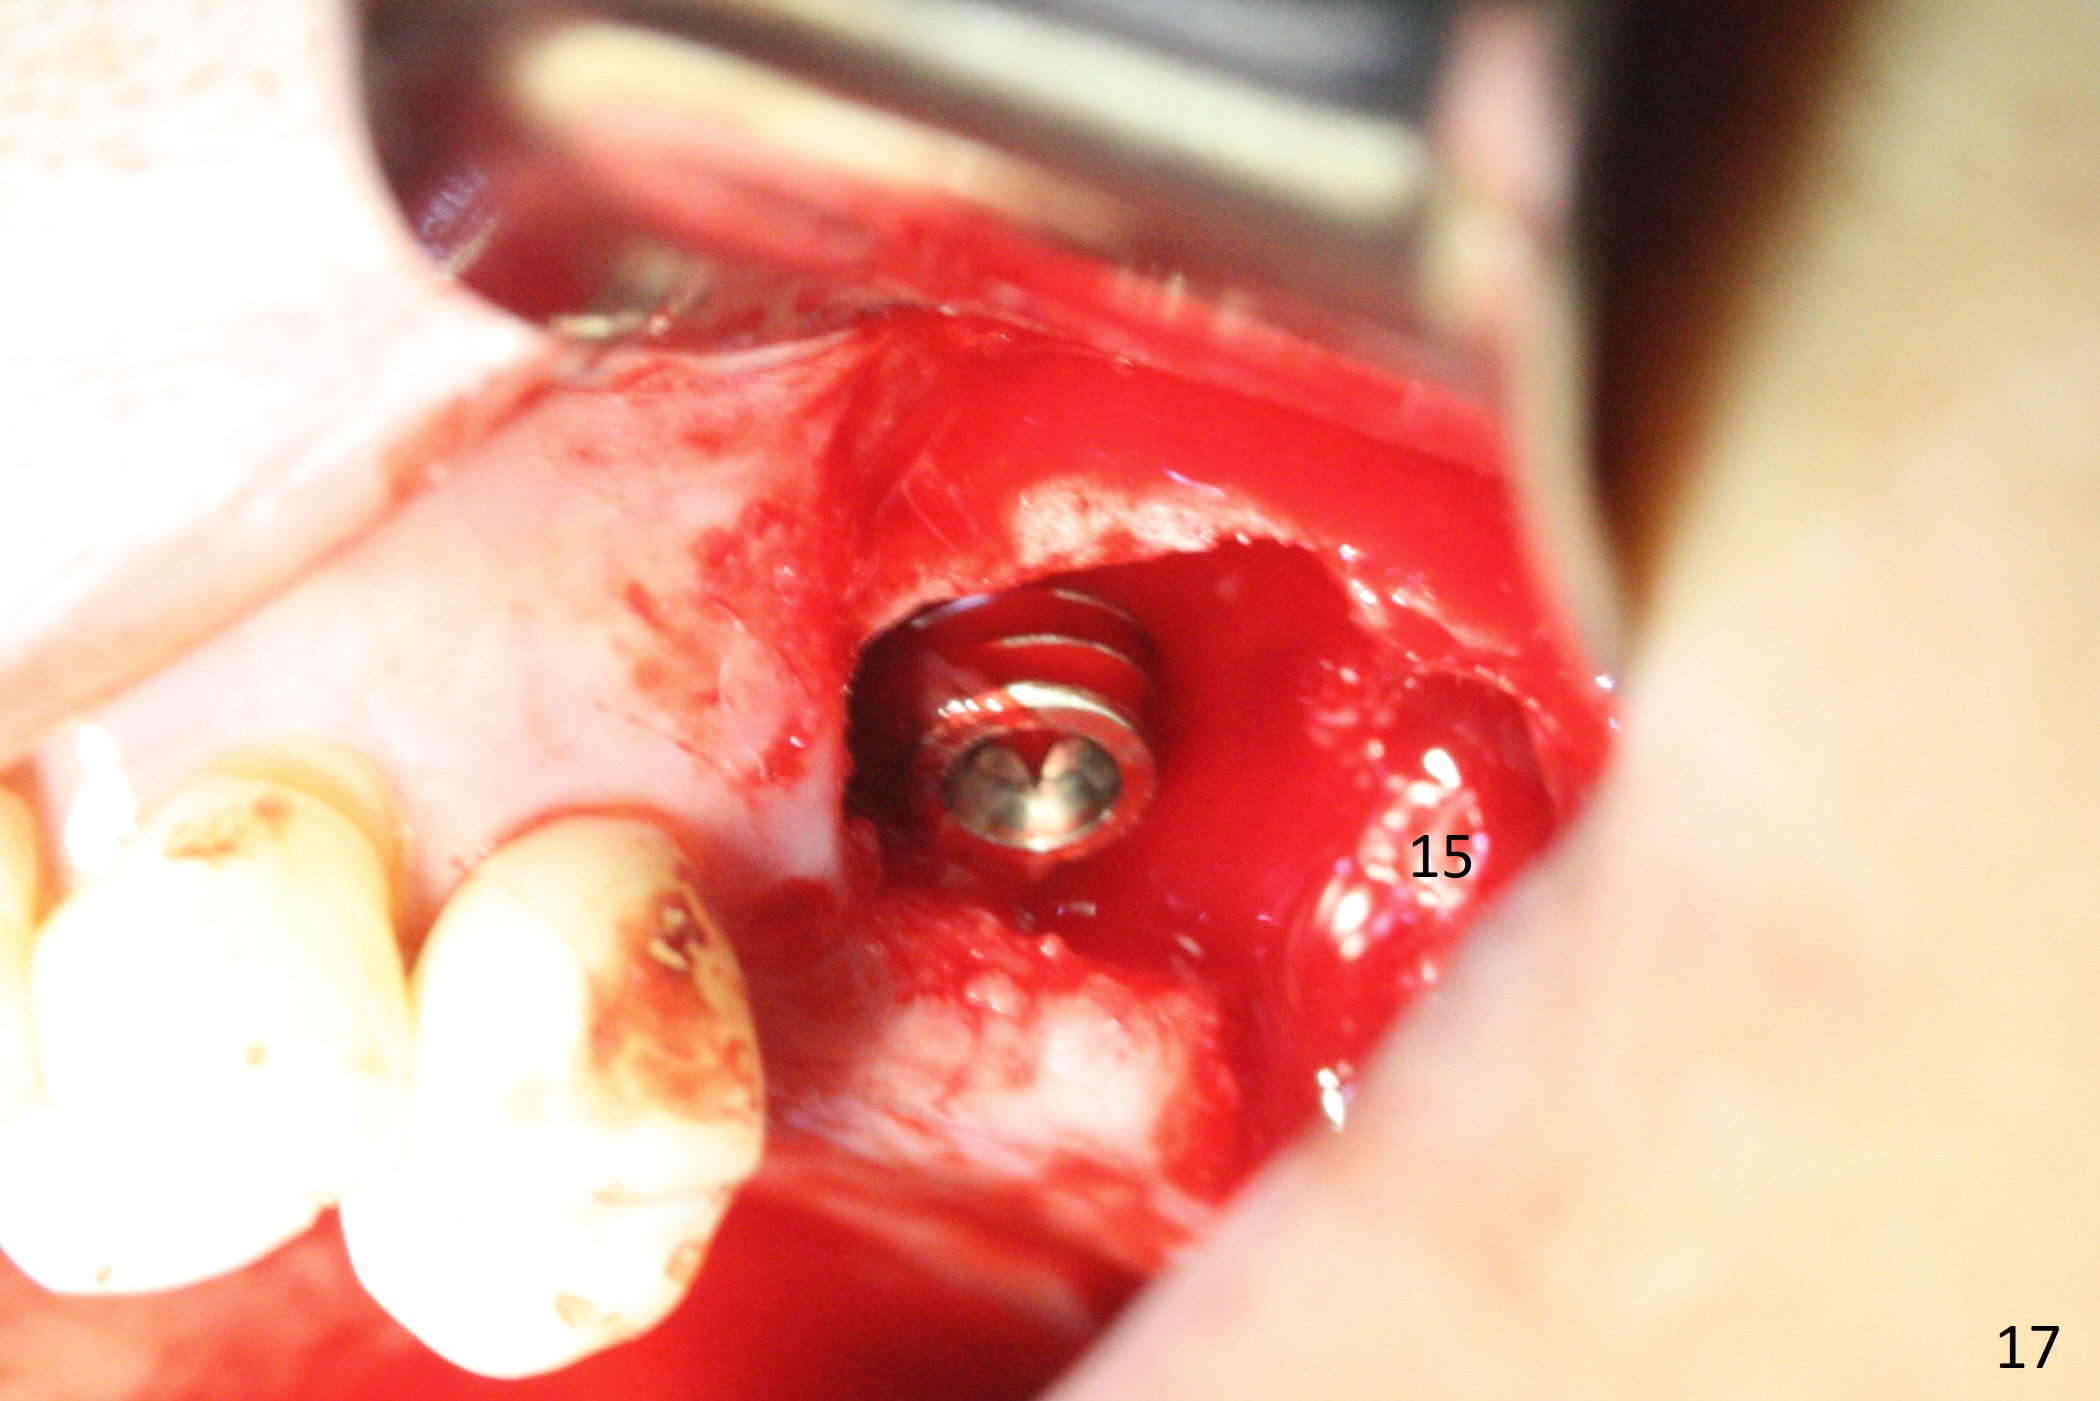

The amount of the bone graft mesial and distal the implant seems to reduce 3 and 4 months postop, respectively (Fig.6,7 arrowheads). When the acrylic is cut off 4 months postop, the bone graft is loose. The gingiva is unhealthy. The abutment and implant are loose. A healing abutment is placed (5x4 mm). The implant is torqued to 35 Ncm 6 months postop with the healing abutment reapplied. The patient will return for follow up nearly 9 months postop. A larger healing abutment will be used if the implant is stable. Two weeks later, use a smaller restorative abutment for easy impression. In fact the implant is unstable with #15 mesial shift due to abnormal occlusion with #17 (Fig.8). Bone density around the implant is low (* in Fig.9 (PA), 10,11 (CT sagittal, coronal sections)). A healing screw is placed for self healing. A 2nd option is to remove the implant (Fig.12), BEB (Fig.13) and place the implant deeper (Fig.14) or larger one (5.5-6.5x13 mm). The 3rd option is to place larger and longer implants (Fig.15 (tapered), 16 (cylindrical)). The implant access has partially closed 14 months postop, but there is a small buccal opening with sanguine exudate. Incision reveals severe bone loss around the implant; the mobile tooth #15 is extracted (Fig.17). After debridement and irrigation with normal saline, Vera Graft (Fig.18 *) and Collagen plug are placed with periodontal dressing.